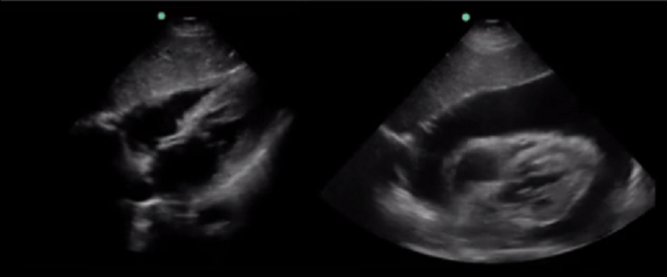

Bild: RUSH, Perikardflüssigkeit, Vergleich Ja/Nein